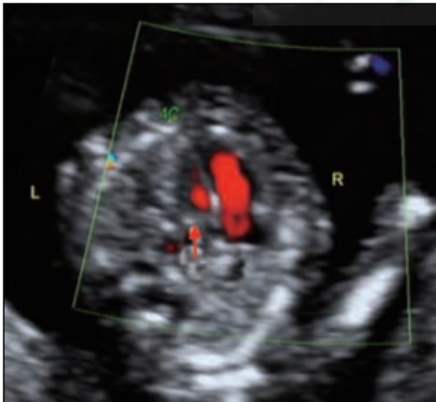

孕媽媽特別關(guān)注的心臟篩查也包含在內(nèi),可以從不同切面觀察心臟結(jié)構(gòu)。同時,對胎兒面部、顱腦、脊柱、胸腹部和四肢等結(jié)構(gòu)逐一排查。部分嚴(yán)重的胎兒結(jié)構(gòu)異常在妊娠11~13+6周可以被早期發(fā)現(xiàn),如無腦兒、無葉全前腦、單腔心、腹裂、巨型臍膨出、肢體缺如、聯(lián)體雙胎等,無需等到妊娠20-24周大排畸。

孕13+4周四腔心切面左右心室血流束不對稱